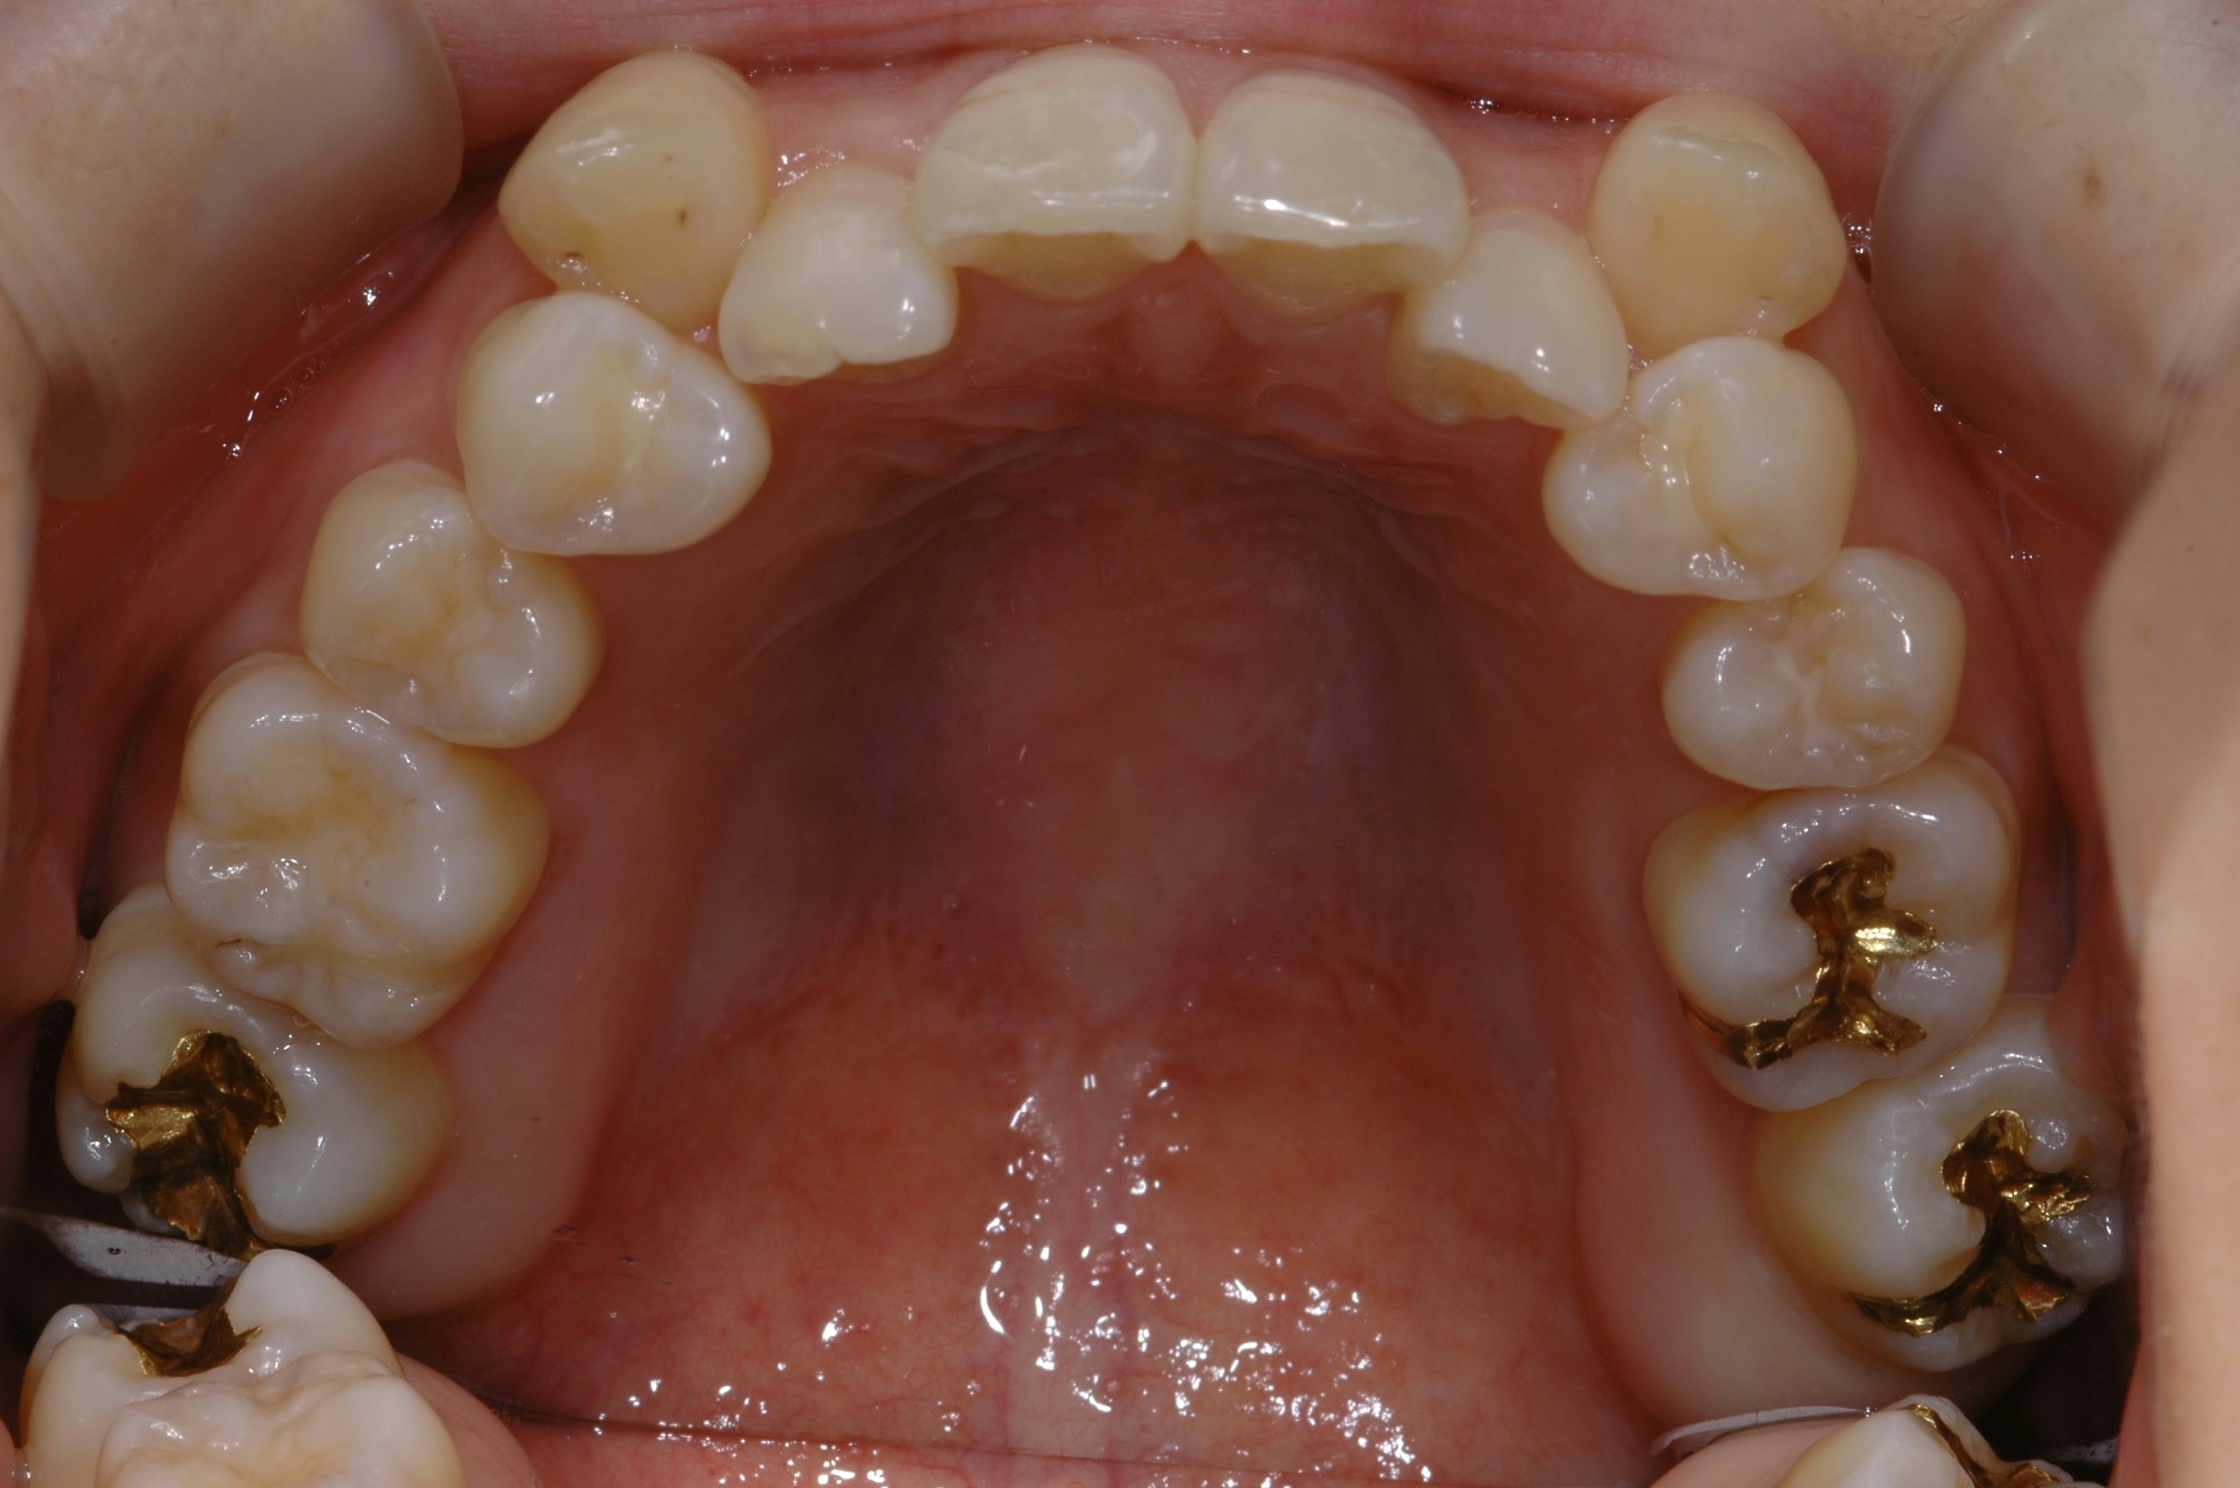

치료 전 사진입니다.